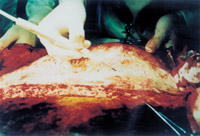

µÚ¶þ²½£º¹Ø±ÕÓúºÏ´´Ãæ

3-7 È¡ÒìÌ寤£¬£¬£¬£¬£¬£¬£¬£¬´ò¶´À­Íø,½«Æä×÷ΪÔÝʱÁýÕÖÎï

3-8 ½«ÒìÌ寤À­ÍøÊ½ÁýÕÖÔÚÊÖÊõºóµÄ´´ÃæÉÏ¡£¡£¡£¡£¡££´Ììºó½«×ÔÌ寤ÇгÉËéÁ££¨»òƬ£©Ç¶ÈëÒìÌ寤µÄÍø¶´ÄÚ

3-9 ´ËºóÓúñ·óÁϰüÔú